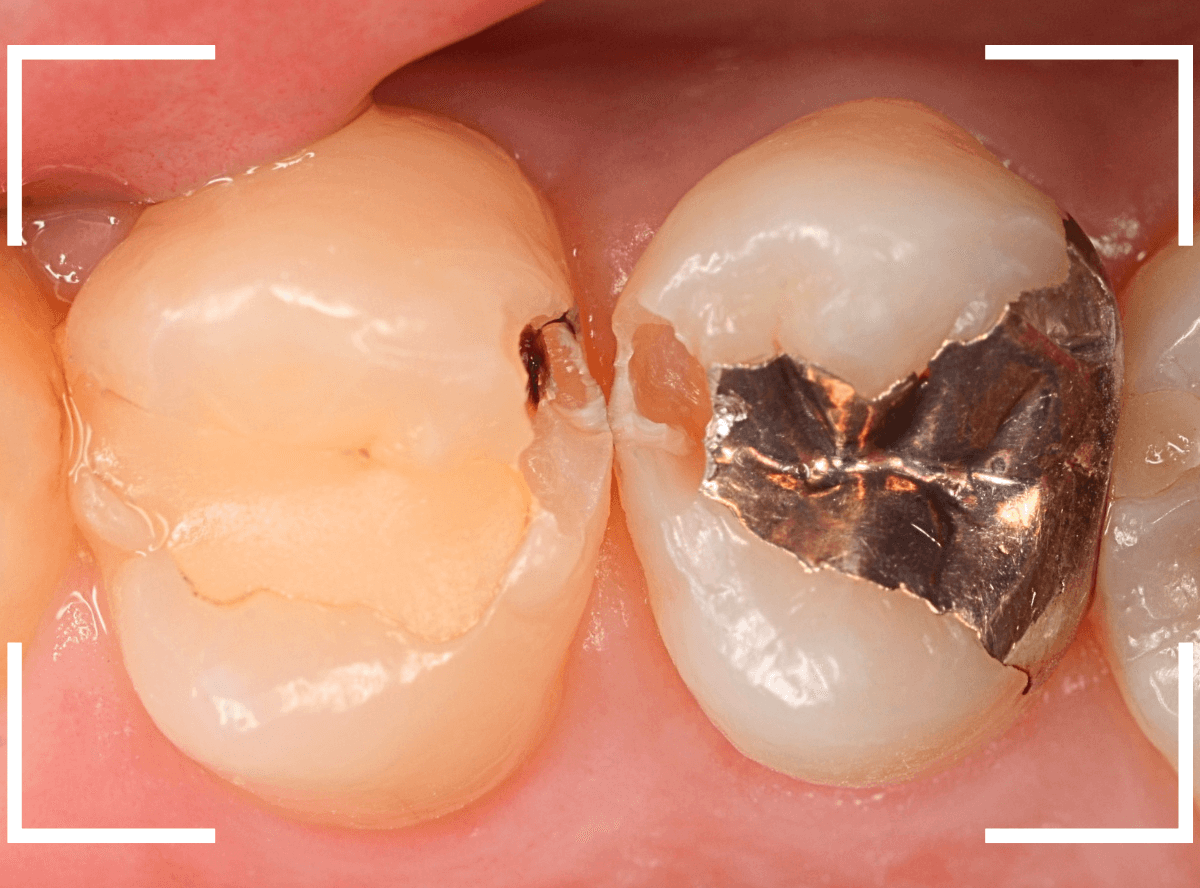

Case.4 レントゲンでわかりづらい、側面の虫歯

検診希望で受診された患者さんです。

歯の溝(裂溝)に虫歯がありそうな歯が見つかりました。

レントゲン写真で確認しますが、虫歯らしき写り方はしていません、浅い虫歯なのでしょうか。

関係ないですが、歯石は確認できますね。

あとは、歯の溝の虫歯を少しずつ除去しながら確認するしかありません。

すると、歯の側面に深めの虫歯が出てきましたので、慎重に虫歯を除去します。

全ての虫歯を除去しました。

今回のように、歯の側面の虫歯は、通常のレントゲン写真でわかりづらく、意外と深い虫歯になっている事があるので要注意ですね。

今回は、通常のレジン治療で終われました。

側面の虫歯を症状が出る前に見つけられたのが幸いでした。